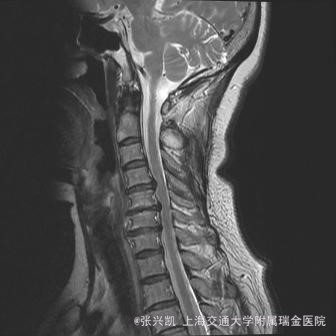

脊柱无畸形,上肢麻木,下肢乏力感。左下肢及前臂较严重,肌力肌张力可,反射存在,下肢感觉正常 。hoffman(+).巴氏征(+) 颈椎MRI示:C4-C6椎间盘突出,脊髓受压,颈椎后凸失去正常生理曲度

诊断:C4-5,C5-6椎间盘突出 治疗:颈椎前路减压融合内固定术